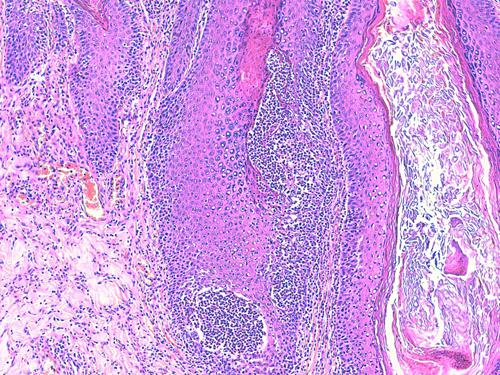

Photo 2 (Hémalun Eosine X 100) peau velue : Vue rapprochée de la Photo 1,

sur un infundibulum folliculaire criblé de pustules pariétales microloculaires.

On note une hyperkératose orthokératosique de l’infundibulum adjacent.

Légendes de la Photo 2 :

- Double flèche bleue pointillée : grand axe des infundibula folliculaires

- Double flèche verte : derme

- Étoiles rouges pleines : erreur (!)

- Ovales jaunes : pustules folliculaires pariétales (folliculite murale)

- Étoiles vertes évidées : lumière des follicules pileux, à gauche parakératosique, à droite orthokératosique